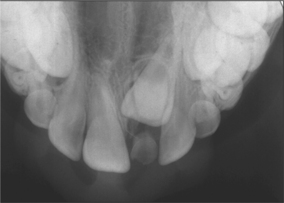

2. The patient in Fig. 12.17 presents with failed eruption of the permanent upper central incisor.

(a) At what age should this tooth have erupted? List four causes of delayed eruption.

Page 181

(b) List three local complications of surgery in this region to expose the tooth.

(c) What is the radio-opacity overlying the tooth crown?

image

Fig. 12.17 See question 2.